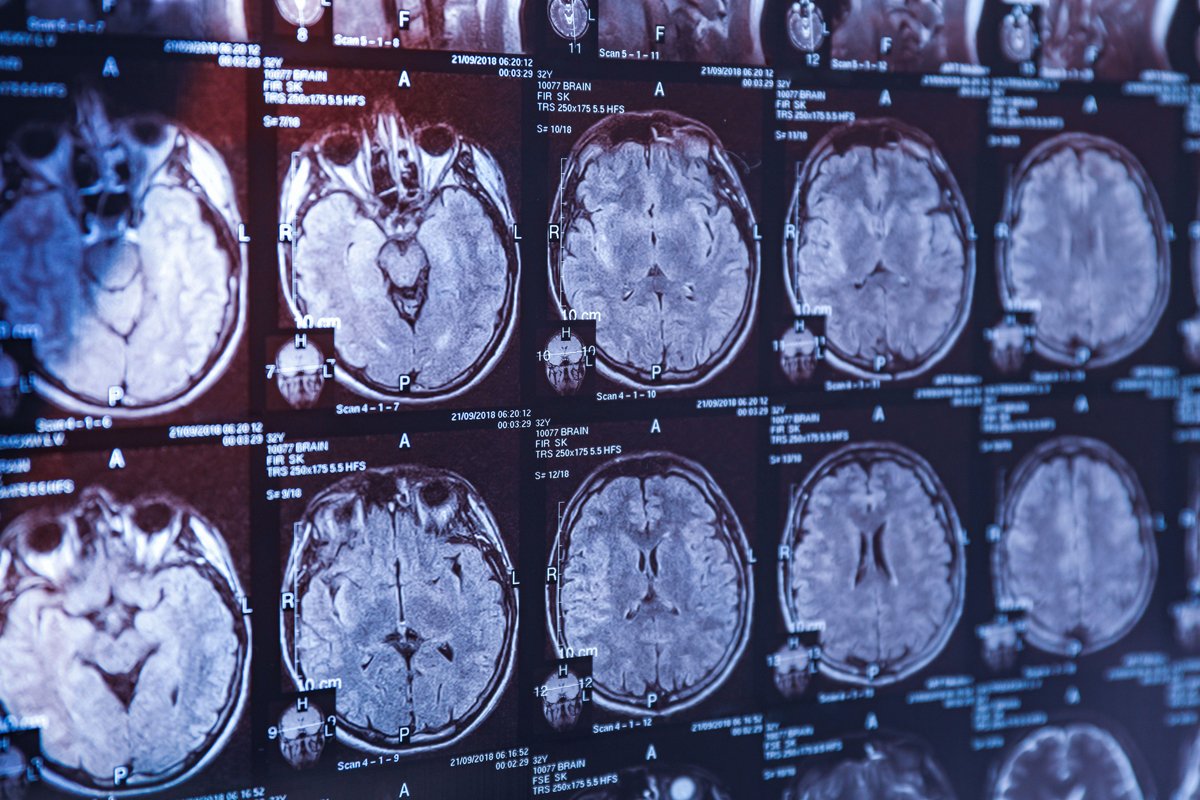

Мозг прооперирует наноробот

Микро- и нанороботы могут решать массу задач в медицине — доставлять лекарства в самые труднодоступные органы и ткани или проводить хирургические операции там, где человек-хирург бессилен. Например, при кровоизлиянии в мозг — состоянии, которое требует немедленного реагирования, а в тяжелых случаях и вмешательства нейрохирурга. Наноробот с этой задачей может справиться лучше, поскольку для него не существует слепых зон и он может выполнять процедуры на клеточном уровне. Самый тонкий момент в этом — точная навигация: как заставить робота перемещаться по кровеносным сосудам в заданном направлении и без вреда для них. Ведь кровоток может вынести наноробота совсем не туда.

Эту задачу удалось решить исследователям из Университета Саскачевана под руководством профессора Криса Чжана. Ученые полностью пересмотрели принципы взаимодействия жидкости и твердого тела, доказав, что они оказывают влияние друг на друга в процессе движения. Далее на основе физико-математического анализа исследователи рассчитали оптимальные размеры и форму «виртуального хирурга». В результате был сконструирован наноробот спиралевидной формы, благодаря которой он может продвигаться в сосудах вращательными движениями, подобно штопору. Такая модель позволяет достигать самых мелких кровеносных сосудов в самых труднодоступных участках головного мозга и устранять нарушения.

В ближайшее время ученые планируют клинические испытания своей технологии. Если все пройдет успешно, медицина сможет справляться не только с последствиями геморрагического инсульта, но и с неоперабельными опухолями головного мозга, до которых хирургический скальпель не может добраться.